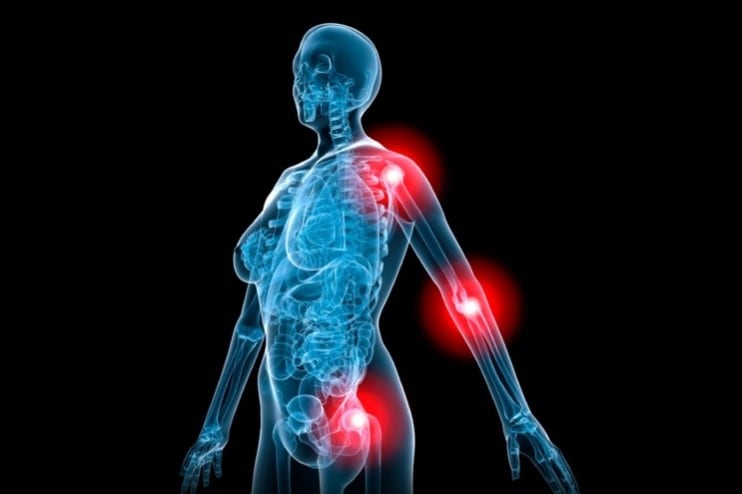

“Joint discomfort is something that almost everyone experiences at some time in their life. You could say that movement controls your happiness in a big way,” he said.

The trial, published in the International Journal of Basic & Clinical Pharmacology, recruited 120 healthy patients suffering from mild to moderate osteoarthritis and divided them into three groups: One using the Easy Climb product, a second group that used a product that contained the Easy Climb constituents with a low dose of glucosamine, and a placebo. Rajendran said the glucosamine was included because many consumers and potential customers are still looking for this ingredient and his company wanted to see if it was possible to have it still be effective at a lower dose by combining it with teh support of the synergistic herbal blend.

The study found that some subjective measures of pain and stiffness improved across all three groups. But they noted that a big placebo effect is often observed in joint health studies when looking at these measures. It’s in the functional measurements where the proof is found in the pudding, teh authors said.

“Both supplements resulted in an improvement in the 30 second chair stand test results, WOMAC pain scores, knee flexion, and joint space width as measured by X-ray, as compared to the placebo,” they concluded.